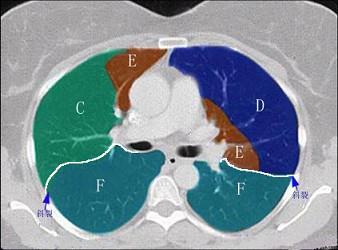

结合肺段模式肺动脉干与右肺动脉层面(如图),选出右肺中叶的组成 ( )A.BB.B+CC.B+C+DD.D+EE.D+E+F

问题 结合肺段模式肺动脉干与右肺动脉层面(如图),选出右肺中叶的组成 ( )

选项 A.B B.B+C C.B+C+D D.D+E E.D+E+F

答案 D